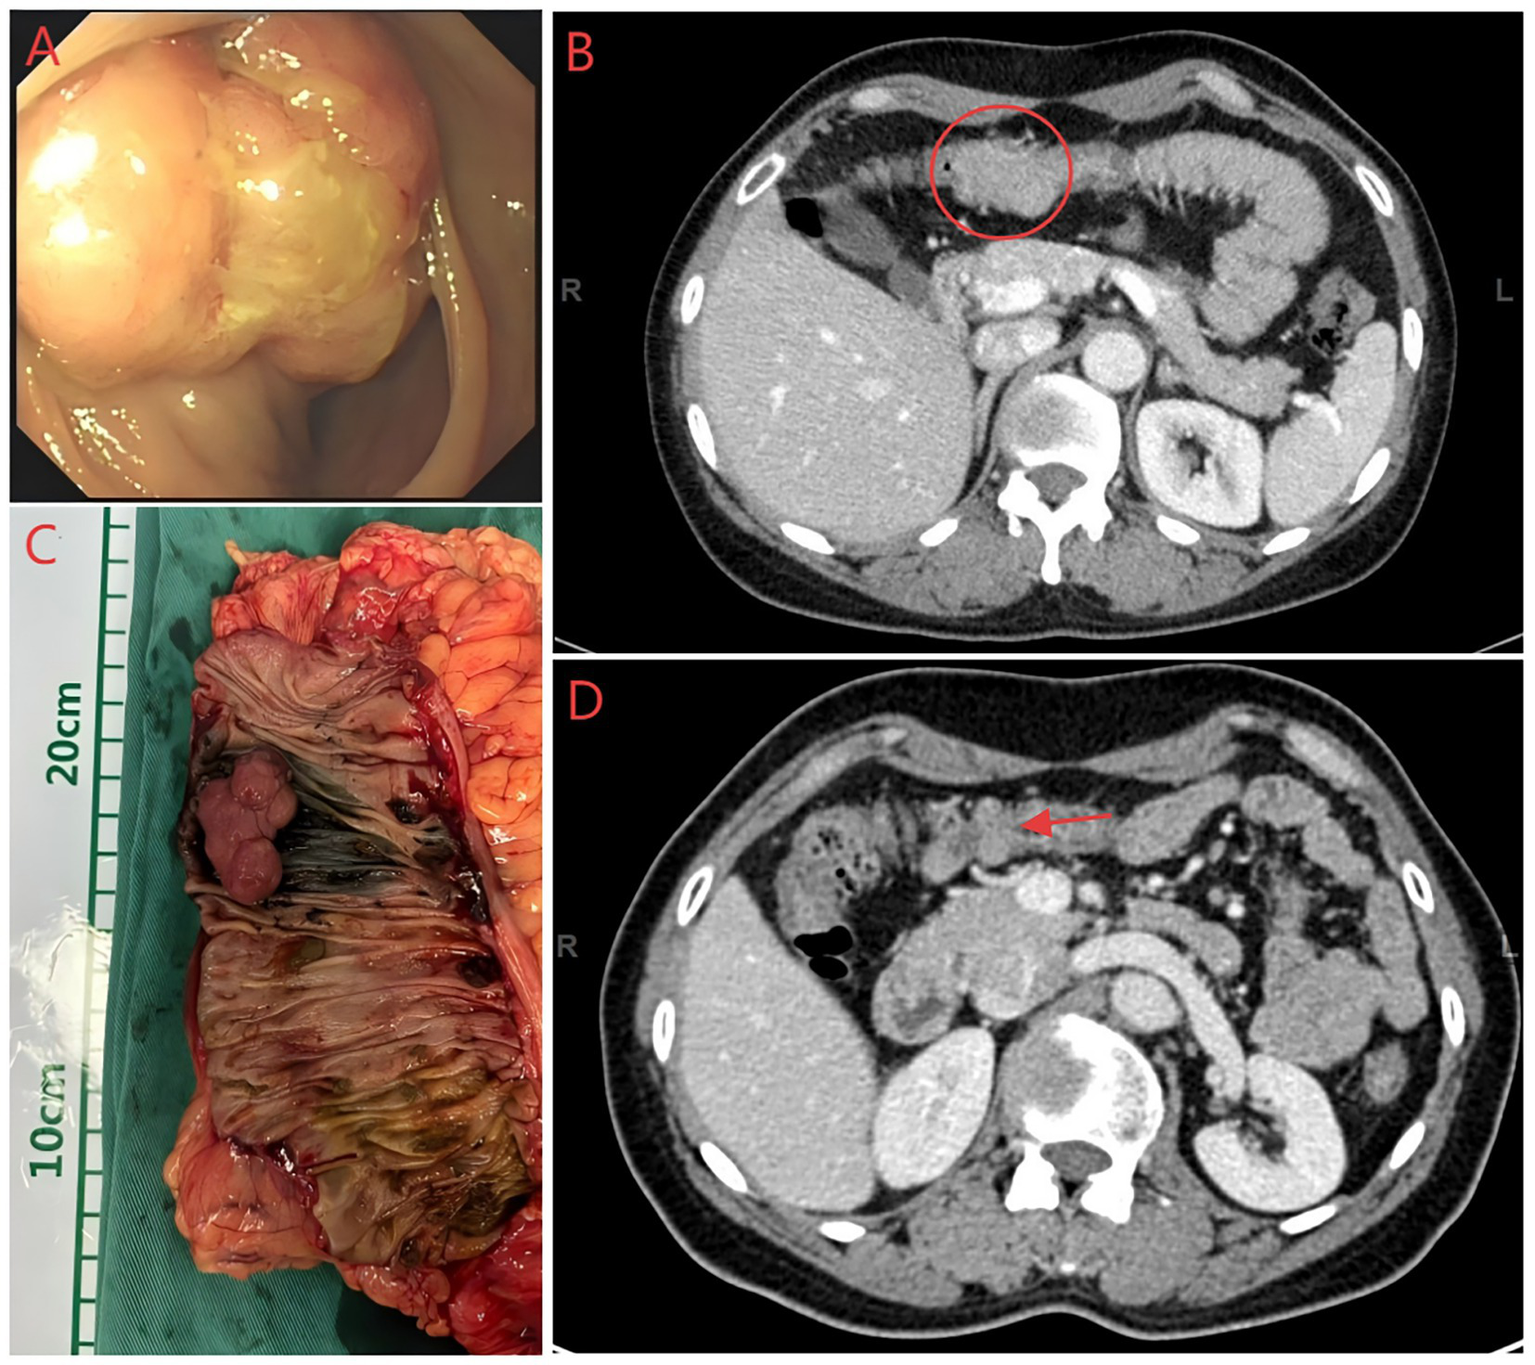

Figure 4

Colonoscopy, CT and colon specimen image of the patient. (A) Colonoscopy image of the patient. (B) Abdominal CT images before the second surgery, the mass is located within the red circle. (C) Intestine specimen after radical right hemicolectomy (A mass was pink with a 4 cm diameter). (D) Abdominal CT images before the first surgery, the area indicated by the red arrow is the suspected mass.

Surgical excision of the mass is considered the best treatment option. On 25 December 2023, the patient underwent surgery; to ensure a clean margin and complete tumor resection, the surgical treatment involved hysterectomy, bilateral adnexectomy, excision of the upper part of the vagina (Figure 2), and lymph node dissection. The surgery and postoperative courses were uneventful. On 30 December 2023, the postoperative pathological result suggested a moderately differentiated endometrial carcinoma of the vaginal fornix, and endometriotic components were observed around the tumor. The lesion involved the full thickness of the vaginal wall, with a close but clean deep margin. No malignant features were observed in the severed end of the vaginal wall, and no tumor plugs were seen, including uterine adenomyosis, atrophic endometrium, chronic inflammation of the bilateral fallopian tubes with left parovarian cyst and simple cysts of the left ovary, and no lymph node metastases (Figures 3A–E). Based on the pathological findings, the patient was ultimately diagnosed with EAM and staged as FIGO Stage IA (with reference to vaginal carcinoma). Immunohistochemistry revealed the following: MLH1(+), MSH2(+), MSH6(−), PMS2(+), ER(+), PR(+), P53(focal+), P16/mtsl(partial+), Vimentin(partial+), CEA(−), and Ki-67 (30%) (Figures 3F–K). Due to a total loss of expression of the MSH6 protein, the patient underwent genetic sequencing. On 3 January 2024, we initiated a paclitaxel/carboplatin (TC) regimen (paclitaxel 175 mg/m2 + carboplatin AUC 5) as postoperative chemotherapy. The first chemotherapy cycle was uneventful. On 17 January 2024, the genetic sequencing results showed that MSH6 p. F1104Lfs*11 (c.3312delT) and c.3556 + 1G > A were positive, indicating the presence of germline mutations. These findings strongly suggested a diagnosis of LS. On 20 January 2024, the patient was readmitted for the second cycle of chemotherapy. On 23 January 2024, she underwent a colonoscopy before the second postoperative chemotherapy treatment to rule out intestinal lesions. A mass of approximately 6 cm in diameter was identified in the proximal half of the patient’s transverse colon, and samples were obtained for biopsy (Figure 4A). On 26 January 2024, the patient underwent the second cycle of postoperative chemotherapy. Pathological examination of the biopsied colonic mass revealed a tubular adenoma, with focal glands and high-grade hyperplasia. One month later, the patient was admitted to the Department of General Surgery for treatment. A repeat abdominal CT scan showed a mass measuring 4 cm in diameter in the right half of the patient’s transverse colon (Figure 4B). The two CT images (Figure 4C) were compared, and a senior radiologist was consulted. On 28 February 2024, she underwent laparoscopic radical right hemicolectomy (Figure 4D). Histopathological evaluation of the mass revealed a tubulovillous adenoma with high-grade intraepithelial neoplasia of partial glands. The final staging was TisN0M0. The patient had an uneventful postoperative recovery.